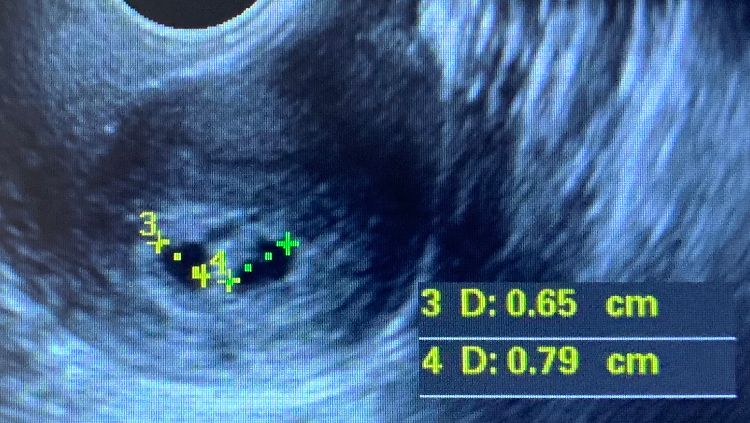

Сегодня из больнички выпустили, на таблетках транексама буду, после 11 дней стационара уже не могу тут. В пн на прием снова и больничный продолжается. Вчера алая кровь была разово на салфетке и сегодня чуть чуть. На узи сегодня 25дпп сказали справа видно развитие и пульсацию. Узист так и не понял что слева… Как будто второе плодное, но пока внутри ничего вроде бы. Либо второй, либо замерший, либо гематома. Подсадка была одного 4АА.

Похоже на 2 плодных яйца!